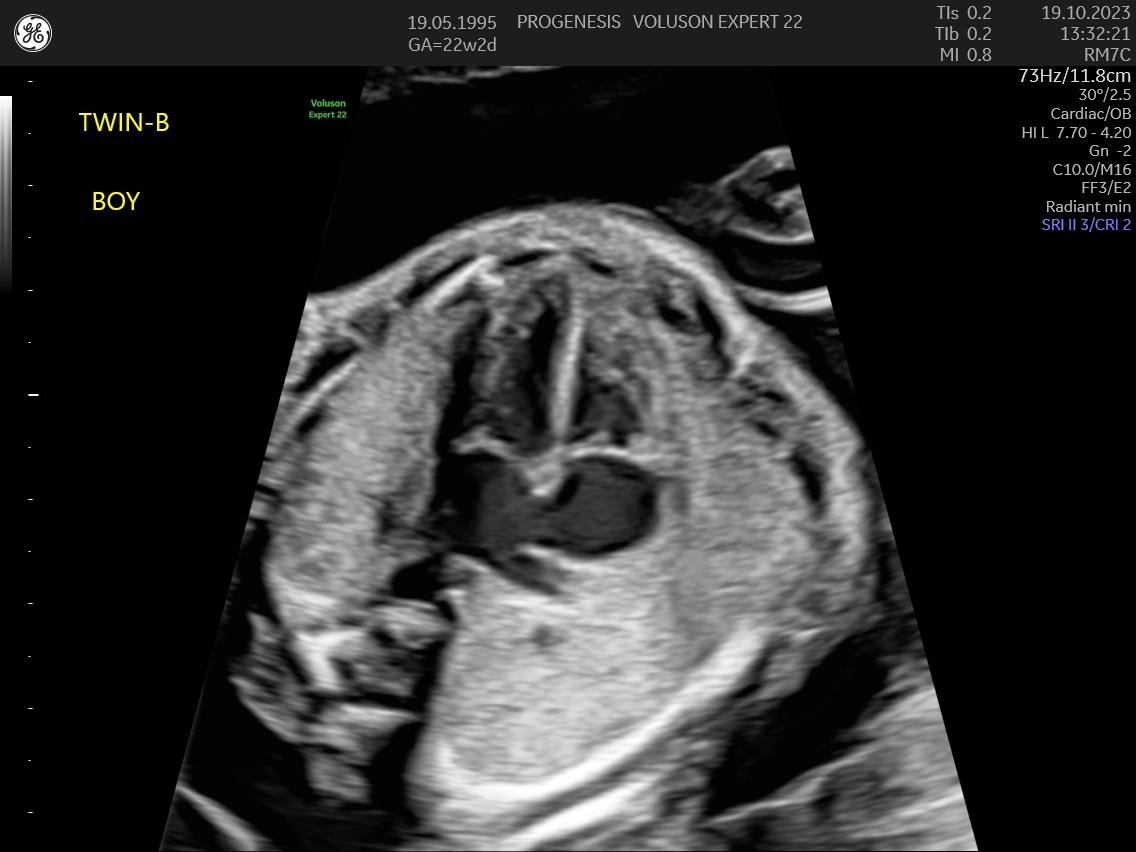

α) Η λεπτομερής αξιολόγηση της εμβρυϊκής ανατομίας, όπου αναγνωρίζονται τυχόν ανατομικές ανωμαλίες.

γ) Ο έλεγχος της ανάπτυξης του εμβρύου, του πλακούντα, του ομφαλίου λώρου και του αμνιακού υγρού.